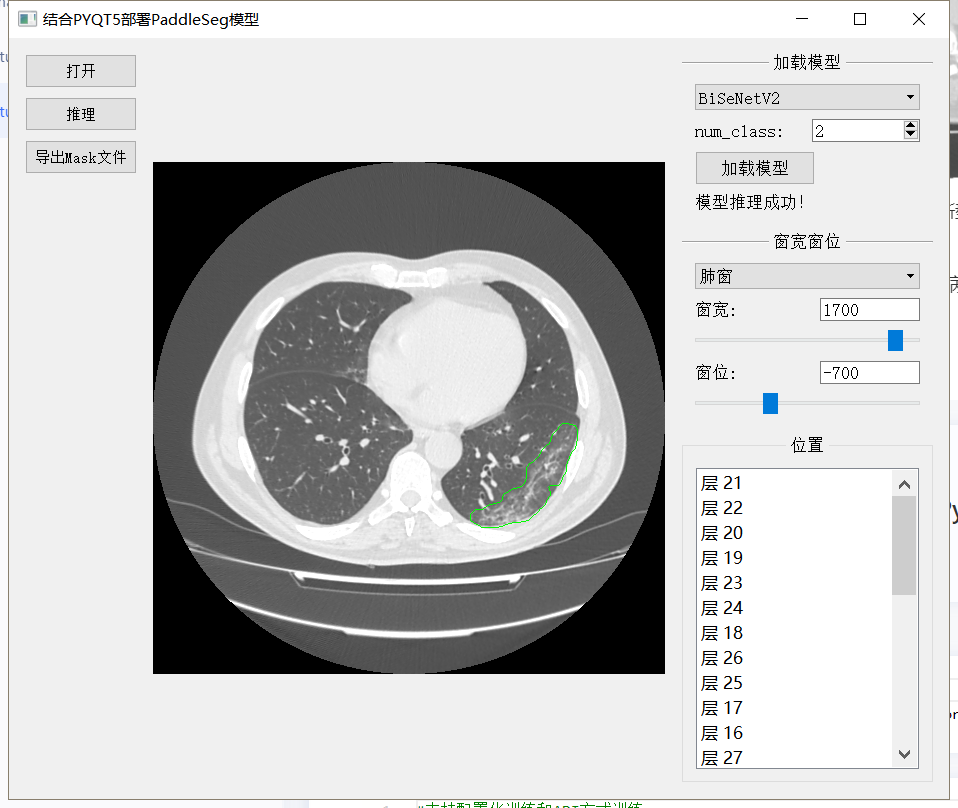

最终结果 结合PyQt制作病灶检测小工具

模型检测效果如下图:

结合PyQT制作小工具效果如下图:

最后结合PyQT制作磨玻璃病灶检测小工具

如图